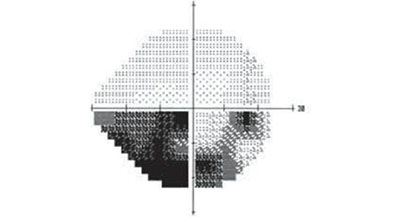

視野決定了眼睛能看到的范圍,如果視野出現(xiàn)缺損(上圖黑色部分),就說明眼睛在黑色部分里是看不見的。